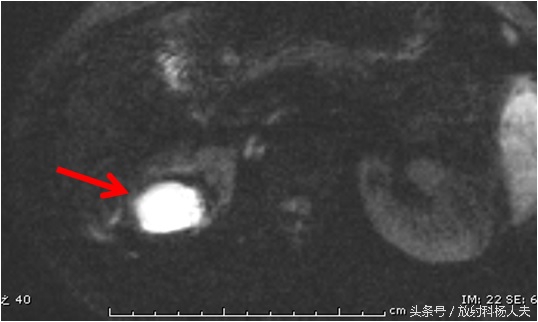

这个囊性病变到底是什么?囊性肿瘤?有无办法继续明确呢?有!那就是MRI,除了进一步明确,还能更清楚的显示窦道的走行。下图这个序列,叫DWI,红箭所示的白白的东西,证明这是一个脓肿!